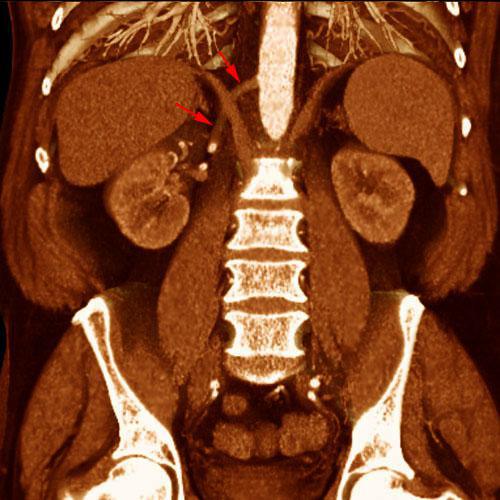

Arterias renales múltiples

Arterias renales accesorias

Arterias renales polares